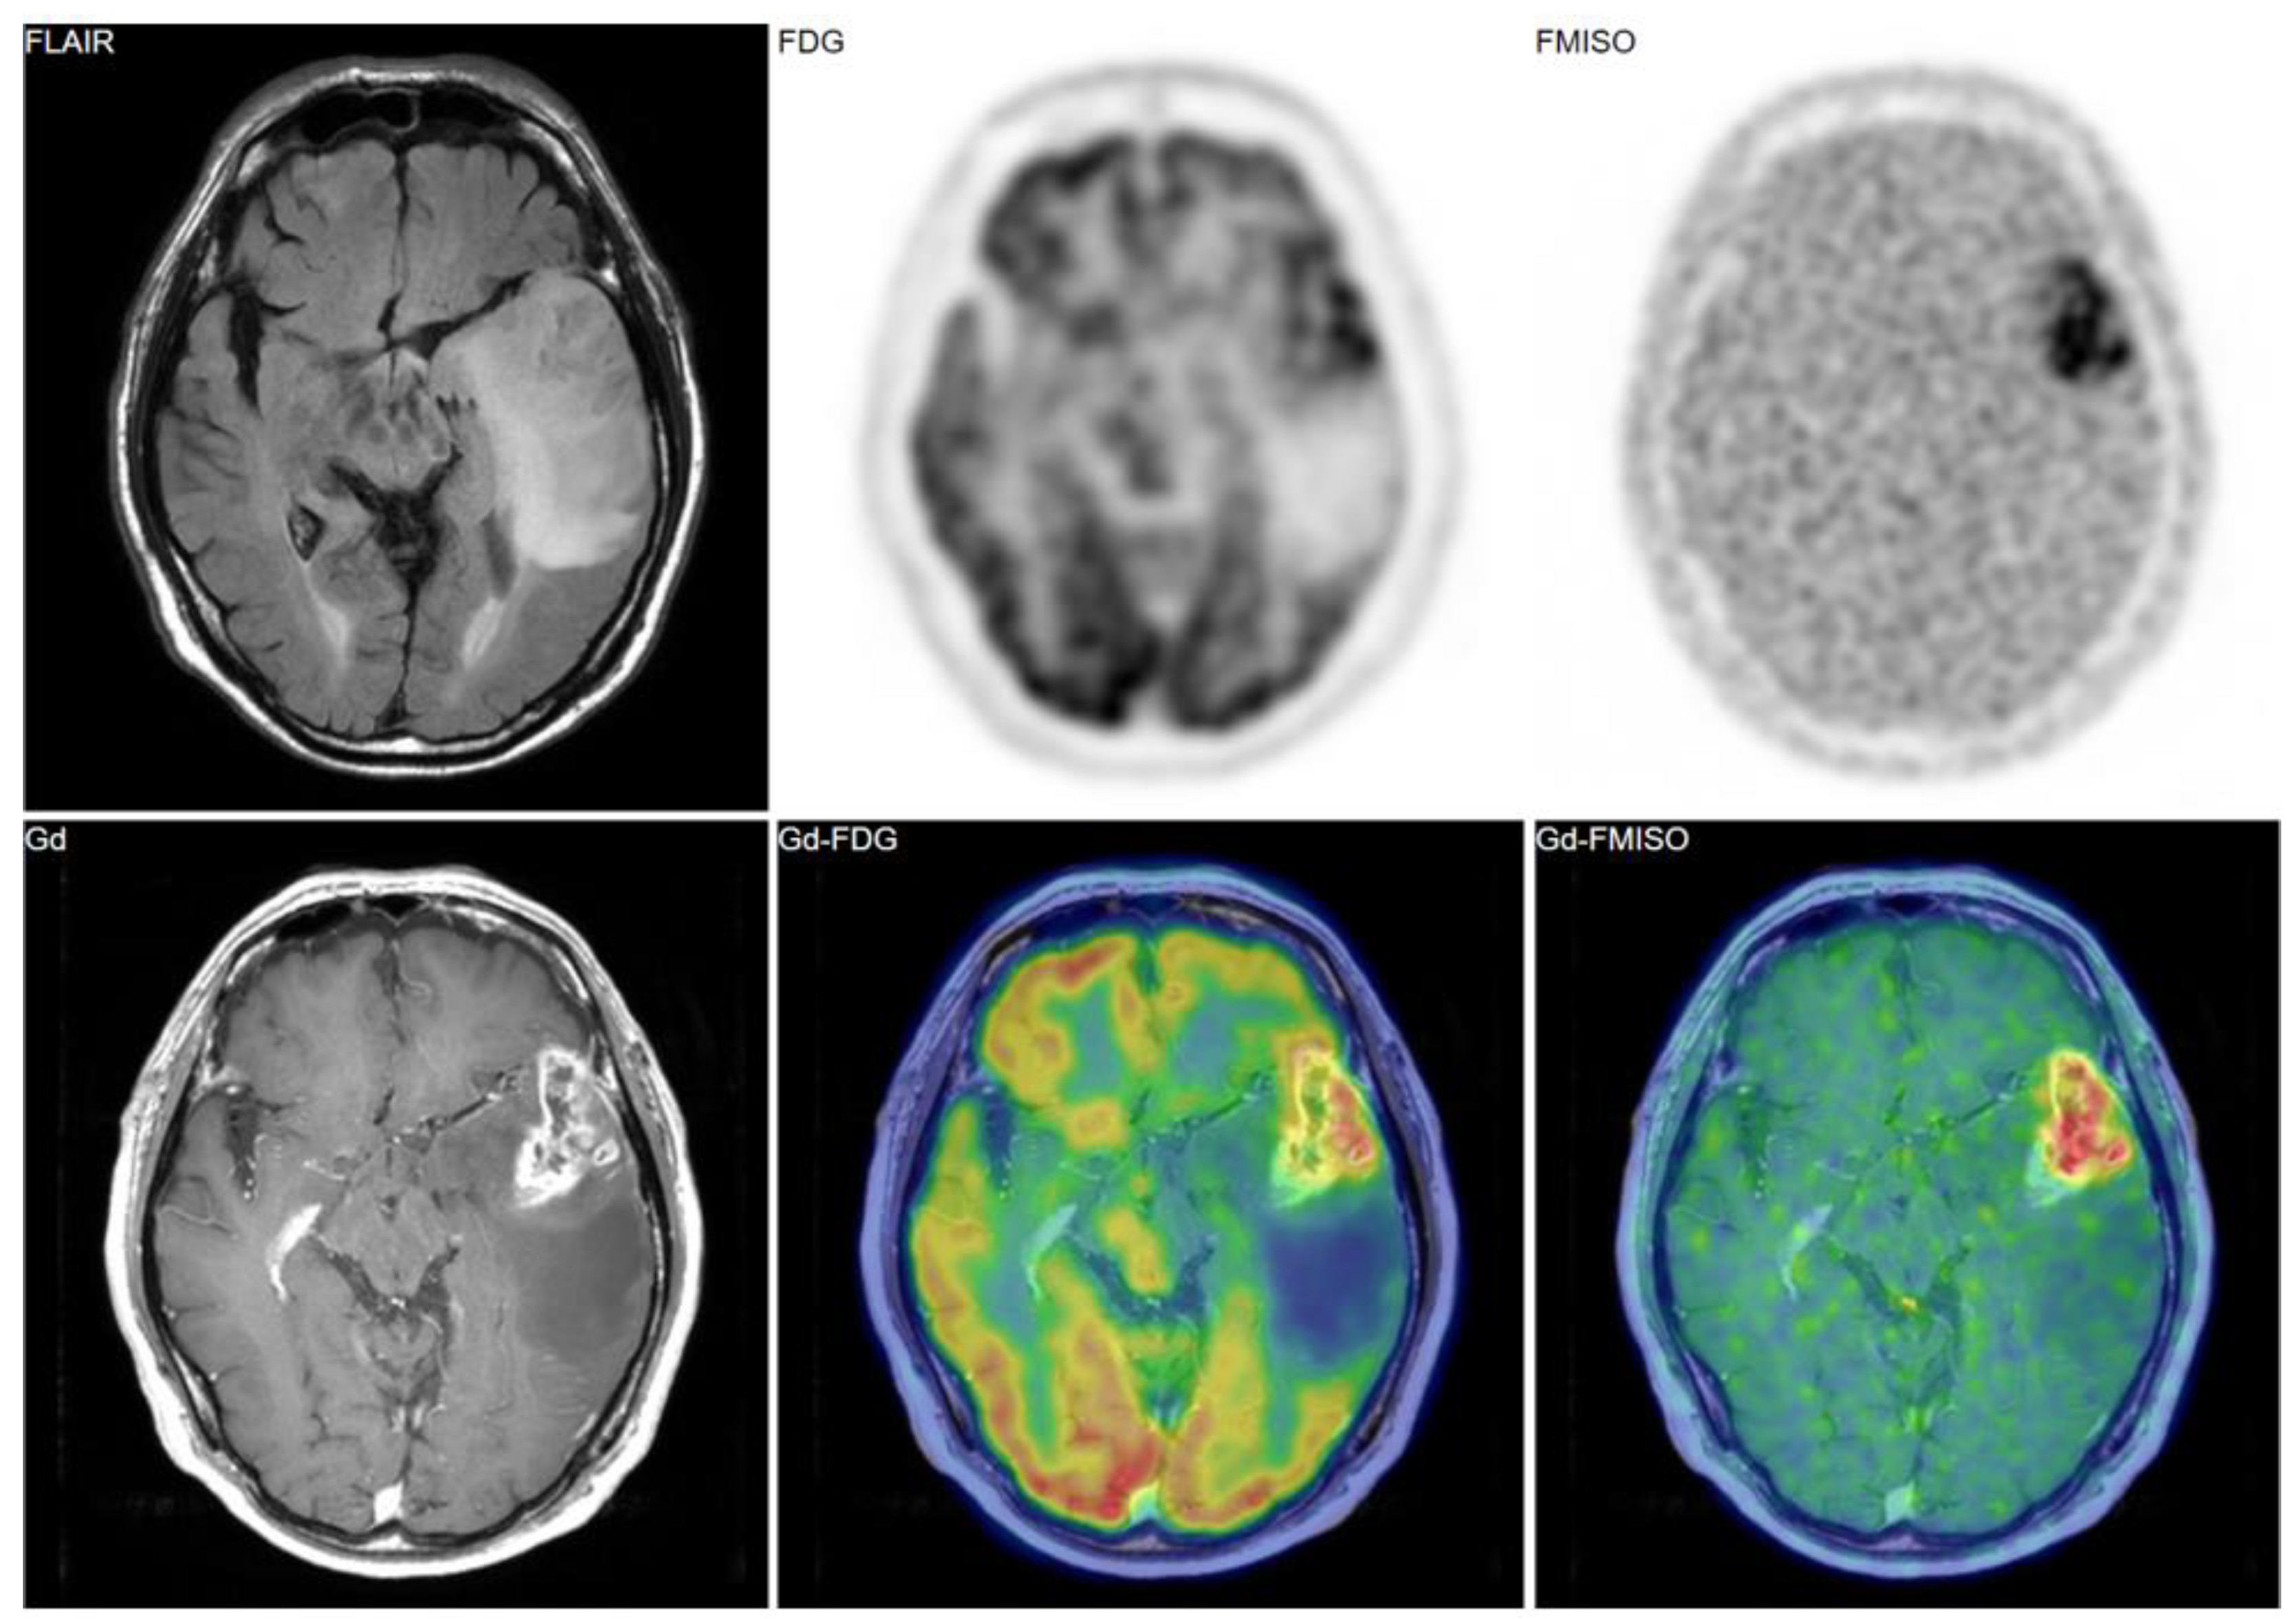

Bevacizumab is a recombinant humanized monoclonal antibody that blocks angiogenesis by inhibiting vascular endothelial growth factor A (VEGF-A) [58]. Although bevacizumab failed to prolong the overall survival of patients with primary glioblastoma [59,60], it was effective in some populations of recurrent glioma patients. In our retrospective study, we investigated whether FMISO PET has the potential to distinguish responders to bevacizumab from non-responders [61]. Eighteen patients with recurrent glioma underwent bevacizumab treatment. We compared the patients’ pre-and post-MRI and FMISO PET to classify them as (1) MRI-FMISO double responders (n = 9, Figure 5), (2) MRI-only responders (n = 5, Figure 6), and (3) non-responders (n = 4, Figure 7). There were no FMISO-only responders. The survival analysis demonstrated that the MRI-FMISO double responders had significantly longer overall survival than the other patients, whereas no significant difference was observed between the MRI-only responders and the non-responders. We thus concluded that recurrent gliomas with decreasing FMISO accumulation after short-term bevacizumab application could derive a survival benefit from the treatment.

Figure 7. A 36-year-old patient with glioblastoma showed no FMISO uptake before the bevacizumab treatment (upper row). After the treatment, the patient presented with the enlarged tumor in the bilateral frontal lobe (lower row). The tumor showed high FMISO uptake. This patient was considered a ‘non-responder’.